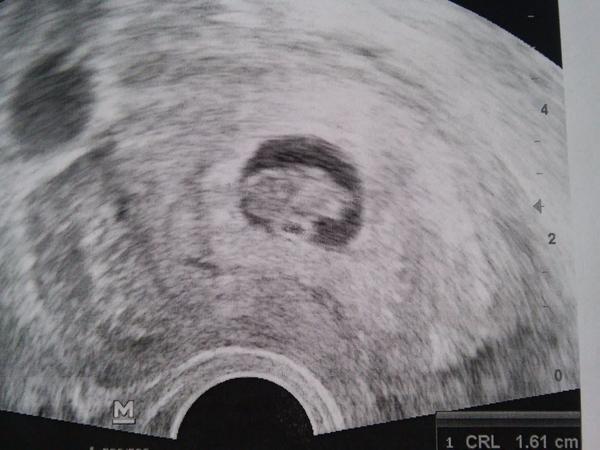

Uff, tak jsem si na tu pohotovost radeji sjela, vse je ok, prcek ma uz 1,9cm a je o dva dny starsi nez dle ms, tak jsem se uklidnila